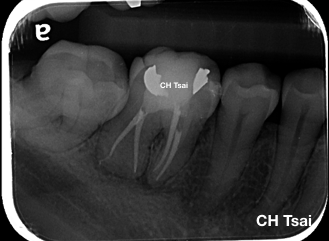

病人因牙髓炎疼痛求診,在治療前的根尖片可以發現右下第一大臼齒遠心根管鈣化;根管的鈣化是牙髓遇到外傷或蛀牙保護的機制,需要有經驗的專科醫師搭配顯微鏡及其他設備的治療,來提高根管治療成功的機會。

在一開始的X-ray中,可見遠心牙根根管極度鈣化,經專科醫師進行顯微根管及超音波療程後,順利完成治療。